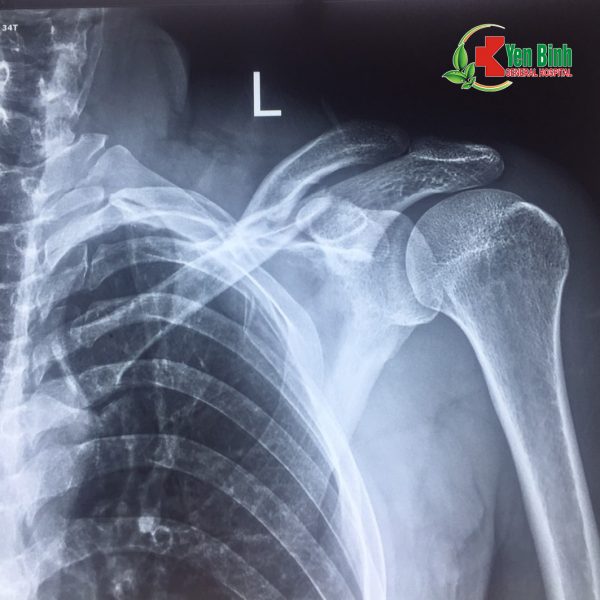

Hình ảnh chụp Xquang xương đòn trái gãy và sau khi đã phẫu thuật cố định xương cho bệnh nhân Hoàng Văn.H

(Hình ảnh do bác sỹ Bệnh viện Đa khoa Yên Bình cung cấp)